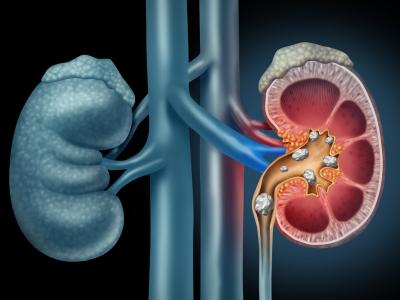

किडनी की पथरी का इलाज, अपनाएं ये 4 उपाय, निकल जाएगी किडनी की पथरी

पथरी में यूं तो कोई परेशानी नहीं होती है लेकिन जब इसका दर्द उठता है तो वो असहनीय हो जाता है। जिन लोगों को किडनी की पथरी की समस्या होती है, उन्हें उसका पता शुरू में नहीं चल पाता। इसके लक्षण तभी दिखाए देते हैं जब किडनी की पथरी का आकार बढ़ने लगता है और यूरीन पास करने में दिक्कत होती है।

डॉक्टर के अनुसार, बहुत महीन आकार की पथरी मूत्र मार्ग से मूत्र निकल जाती है लेकिन कई बार जब ये पथरी नहीं निकल पाती तो एक जगह जमा होने लगती है और पथरी के छोटे-छोटे कण मिलकर एक बड़ा रूप ले लेते हैं। नींबू के रस में साइट्रिक एसिड की मात्रा बहुत ज्यादा होती है जो धीरे-धीरे ऑक्जालेट और सोडियम आदि तत्वों के इस जमाव को घुलाता रहता है। घुलने के बाद पथरी के छोटे-छोटे कण मूत्र मार्ग से ही निकलते रहते हैं।